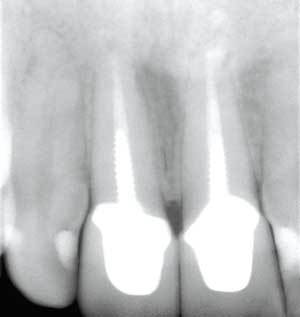

All ceramic crown radiograph. The major drawback in using all porcelain crowns. If you are deciding what type of crown is best for you an all porcelain crown or a porcelain fused to metal crown this blog will help by describing and showing you these types of crowns and explaining their advantages. Note that the copings appear very rounded at the corners a hallmark of all ceramic preparations. A dental crown is a tooth shaped cap that is placed over a tooth to cover the tooth to restore its shape and size strength and improve its appearance.

A porcelain fused to metal crown appears. To have two radiographic components. The smoother surface of all ceramic crowns prevents this common type of wear from occurring. The aesthetics of all ceramic crowns should stay the same as long as the crown lasts.

All resin crowns tend to wear down faster too. A radiograph of a veneered zirconia restoration will show a radiopaque core similar to a metal ceramic crown as shown in figure 3b. All ceramic and all porcelain crowns may look more natural but they re usually not as strong as the metal or porcelain fused to metal versions. Porcelain is a kind of ceramic built by firing and stacking and ceramic refers to porcelain only.